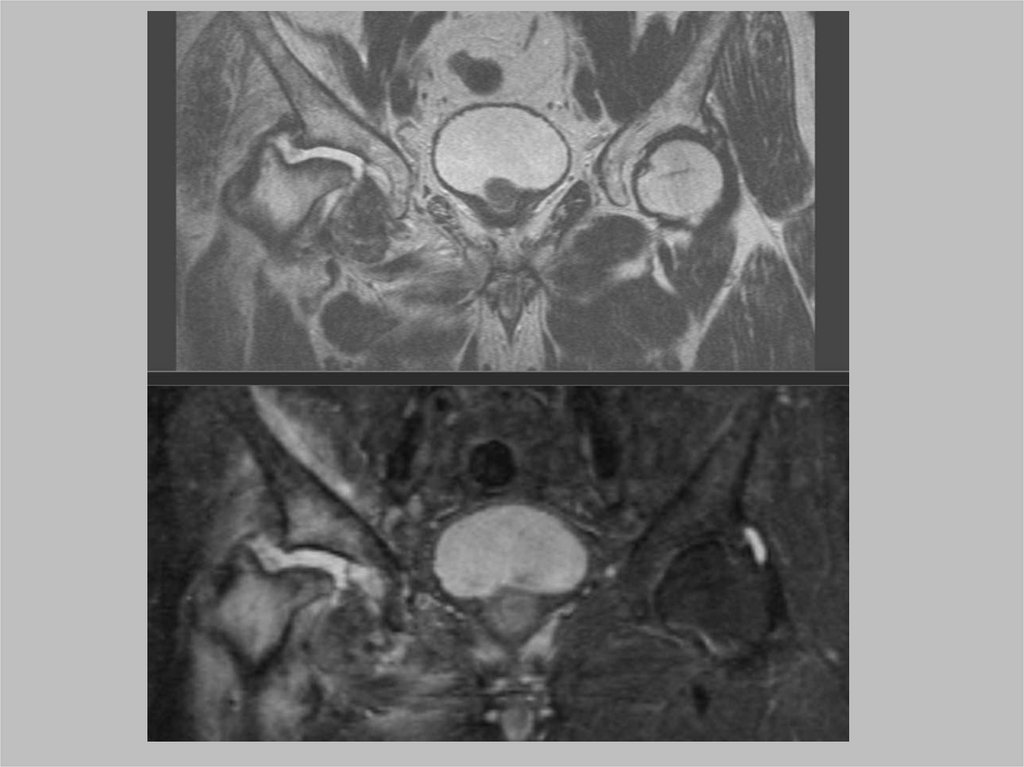

ARS-синдром

ARS синдром – микроразрывы

сухожилий прикрепляющихся к

симфизу и лобковой кости.

Болевой синдром в паховой области у

спортсменов

Вначале имеет воспалительный,

затем - дегенеративнодистрофический характер.

ARS синдром – достаточно

распространенное заболевание среди

спортсменов.

Adduktor-Rectus-Symphysis

• приводящих мышц бедра,

• прямой мышцы живота,

• лонного сочленения.

50.